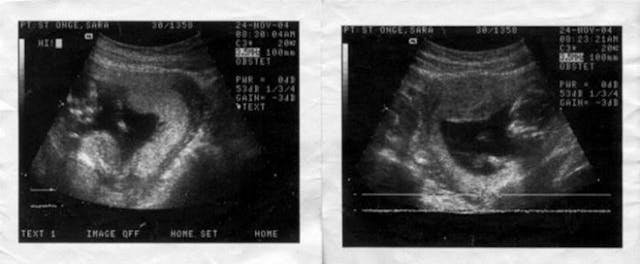

Some health issues affect my memory, but I remember the day I went to see the doctor before my scheduled abortion. I remember praying for forgiveness and hoping that I was making the right decision. I was resolved to go through with it until I heard my baby’s heartbeat. Then the ultrasound technician said, “Your baby seems fine.”